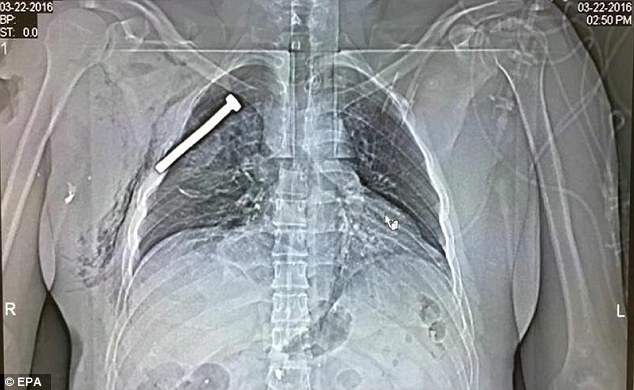

Hetimet kanë treguar se të paktën një nga bombat e shpërthyera sot në aeroportin e Brukselit ishte nga ato që cilësohen si “bombë me gozhdë”.

Bomba në fjalë mbushet me pjesë metalike (vida ose gozhdë) që pas shpërthimit, këto të godasin personat e paprekur nga vala e saj duke u shkaktuar plagë të rënda, deri edhe vdekjen.

Zbulimi është bërë teksa një prej të plagosurve iu nënshtrua një skaneri ditën e sotme në Spitalin Ushtarak në Himbik, ku afër zemrës së tij u gjend një vidë të paktën 5.5 cm të gjatë.